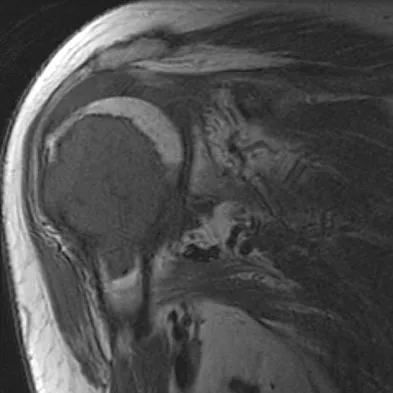

A 58-year-old woman has a fracture through a metacarpal lesion after a motor vehicle accident. She denies any preinjury symptoms and the fracture heals uneventfully. Based on the radiograph and MRI scans shown in Figures 22a through 22c obtained following fracture healing, follow-up management should consist of